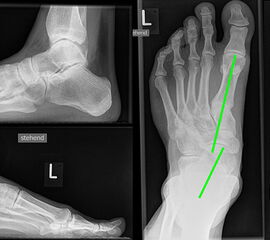

Vermehrter Rückfußvalgus links bei chronischer Instabilität des Deltabandes. Die wichtigste Differenzialdiagnose ist die Insuffizienz der Tibialis posterior Sehne.

Abbildung 2

Bei Insuffizienz der tibionavicularen Bandanteile oder des Spring-Ligaments zeigen die konventionellen Aufnahmen eine Konstellation wie bei einer Tibialis posterior Insuffizienz mit Vorfußabduktion, eingesunkenem Längsgewölbe und vermehrtem Rückfußvalgus (Abbildung 3).